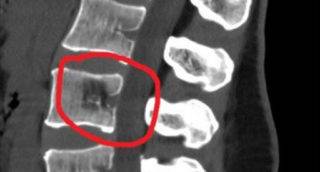

- Под рентген-контролем в позвонок вводят цементирующий состав порциями по 0,5-1 мл. После заполнения позвонка введение раствора прекращают.

У хирурга есть 6 минут, чтобы ввести цемент в тело позвонка под специальной рентген-аппаратурой в скопическом режиме. Спустя 10 минут состав застывает, заполняя трещины и пустоты и укрепляя позвонок.

- Игла вынимается, делается контрольный снимок.

Вместе с полиметилметакрилатом в соединении, которым заполняется позвонок, имеется контрастный компонент. Контраст подсвечен на рентгене, поэтому заполнение контролируется с максимальной точностью. В костном теле позвонка цемент быстро застынет, заполнит все сегменты, где существуют деструктивные изменения.